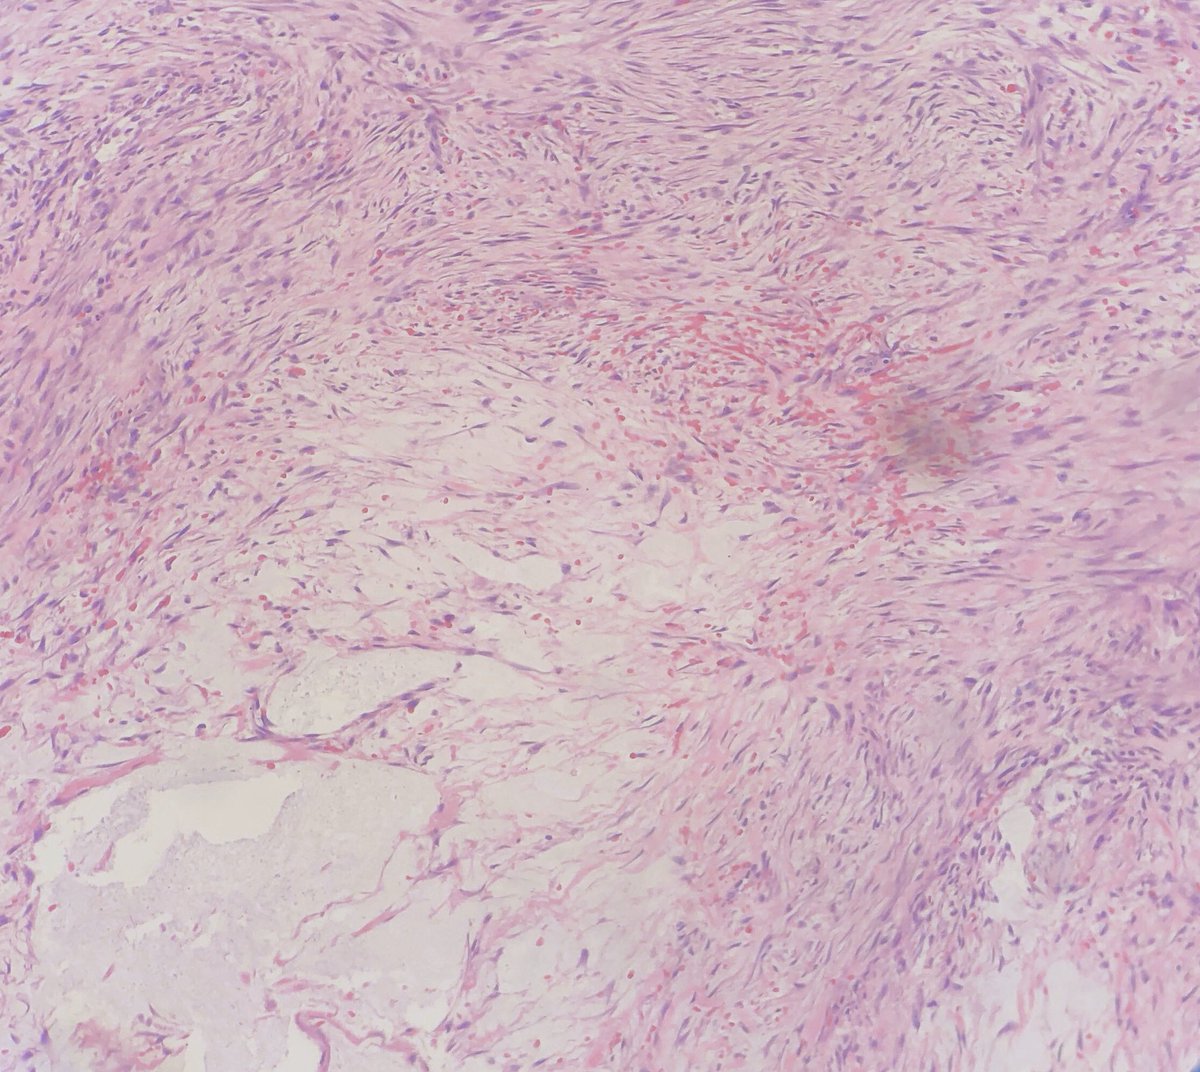

A beautiful

45 year old man with a postauricular mass

spindled and stellate plump cells in fascicular arrangement with myxoid stroma and extravasated RBCs

SMA+, Keratin-, S100-, cytoplasmic b-Catenin

USP6 gene rearranged